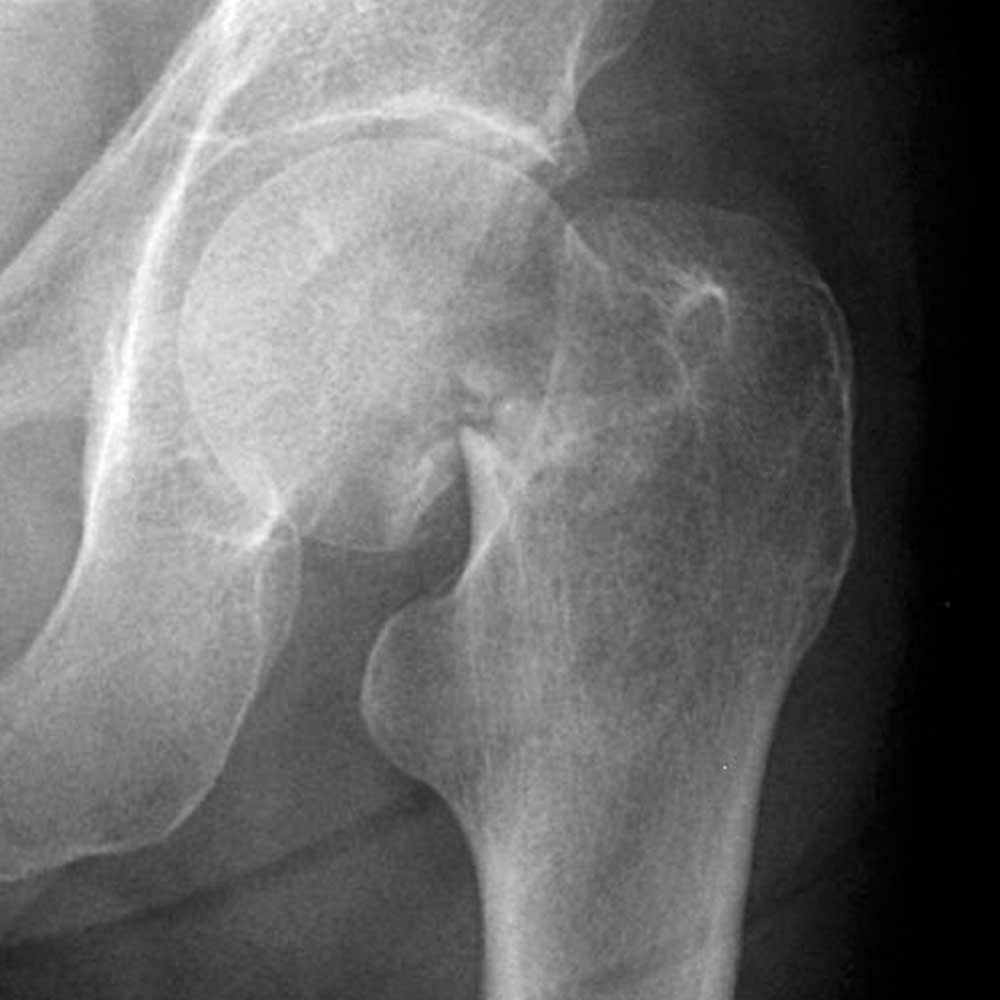

O fractură este o discontinuitate într-un os, apărută brusc prin traumă sau treptat în urma suprasolicitării. Semne care impun evaluare medicală urgentă includ deformare vizibilă, incapabilitate de a folosi membrul, durere intensă care nu cedează, sângerare abundentă, amorţeală, semne de şoc sau rană deschisă cu os vizibil.

- Controlul simptomelor și evaluările radiologice efectuate de profesioniști vor ghida alegerea tratamentului între abordări conservatoare sau intervenționale.